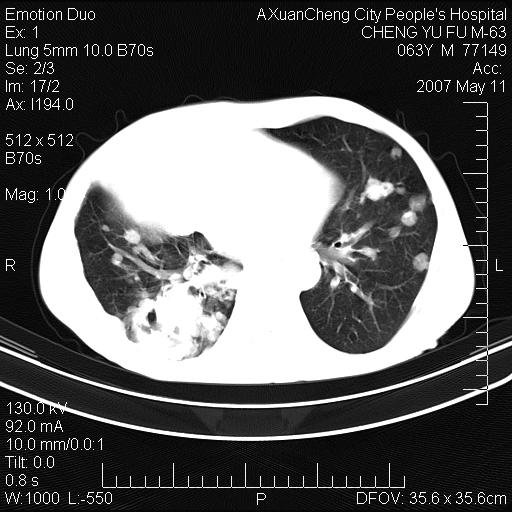

以下是引用小初学者在2007-5-11 19:32:00的发言:[br]1、首先考虑干酪性肺炎支气管播散[br]2、支气管肺泡癌待排

以下是引用zhangzhongshou在2007-5-11 19:30:00的发言:[br]细支气管肺泡癌可能性大。